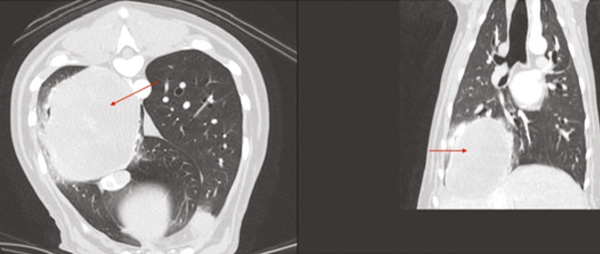

Figure 4: Pulmonary mass (arrows) noted on Computed Tomography.

CT of the thorax and abdomen revealed a large (8.4 x 8.1 x 6.4 cm) pulmonary mass located in the right caudal lung lobe. No metastases were detected.